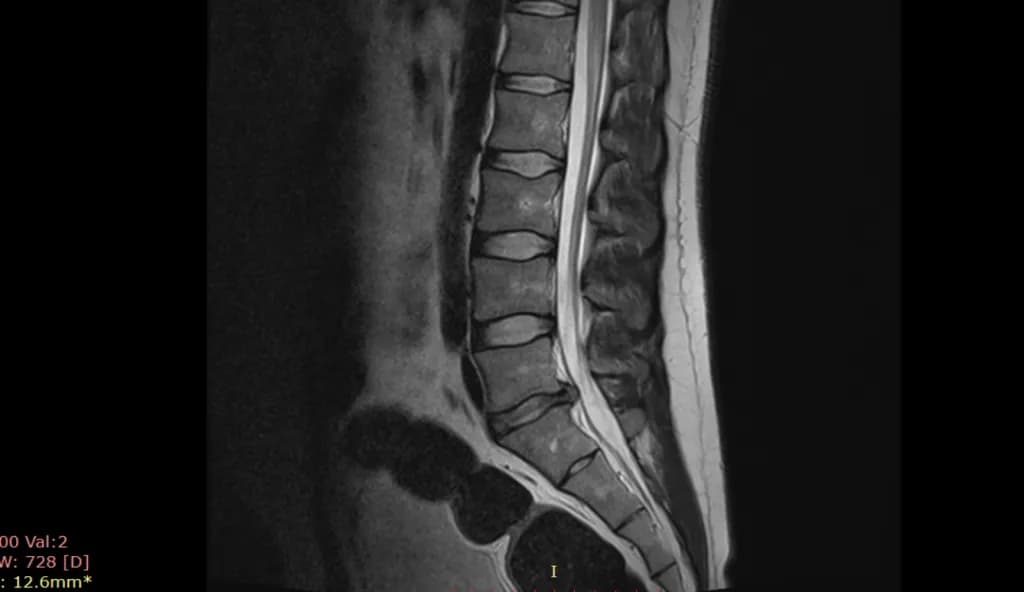

Spontaniczna regresja przepukliny kręgosłupa to fascynujące zjawisko, w którym przepuklina kręgosłupa może się cofnąć bez interwencji chirurgicznej. To naturalna zdolność organizmu do samoleczenia. Proces ten polega na stopniowym zmniejszaniu się wypukłości dysku międzykręgowego, który wcześniej uległ uszkodzeniu.

Cofanie się wypadnięcia dysku to skomplikowany proces biologiczny. Kluczową rolę odgrywają tu komórki fagocytarne - "sprzątacze" naszego organizmu. Te specjalne komórki rozpoznają fragmenty jądra miażdżystego, które wydostały się poza pierścień włóknisty, jako ciała obce.

Po rozpoznaniu, komórki fagocytarne zaczynają "pożerać" te fragmenty. To właśnie ten proces odpowiada za wchłanianie się przepukliny kręgosłupa. Stopniowo, krok po kroku, nadmiar tkanki jest usuwany, co prowadzi do zmniejszenia przepukliny.

Nie każda przepuklina kręgosłupa może się cofnąć, ale wiele z nich ma taki potencjał. Kluczowe znaczenie ma typ przepukliny. Przepukliny sekwestrowane, gdzie fragment dysku odrywa się całkowicie, mają największe szanse na spontaniczną regresję. Z kolei przepukliny protruzyjne, gdzie dysk jest tylko uwypuklony, rzadziej ulegają samoistnemu wchłonięciu.